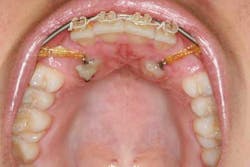

When a full permanent dentition is present (with the exception of impacted canines), the labial/palatal position of the canine will have an influence on what the provider can do. (1) Arguably, obtaining a CBCT is considered mandatory and will allow for a more inclusive treatment plan creation. If angulation is favorable, then consideration to remove the primary canine and wait six months to see if there is movement of the permanent canine is an option. If extraction of the canine(s) is needed, then a premolar substitution, which is dependent on occlusion, can be used in the space. An implant can also be an appropriate alternative. When pulling a canine into the occlusal arch, there is risk involved. Trauma to adjacent teeth (root resorption) and ankylosis are some of the most common complications.The patient was put in full orthodontics and referred to a surgeon for extraction of the primary canines, exposure, and placement of retention on the impacted canines to pull them directly down from their current position.

A ballista appliance was used to prevent a facial pull of the canines in order to avoid and prevent resorption of the roots of the lateral incisors. As movement progressed over the course of the next year, eruption of the canines was considered a success. Once in position, they will be pulled facially into occlusion.